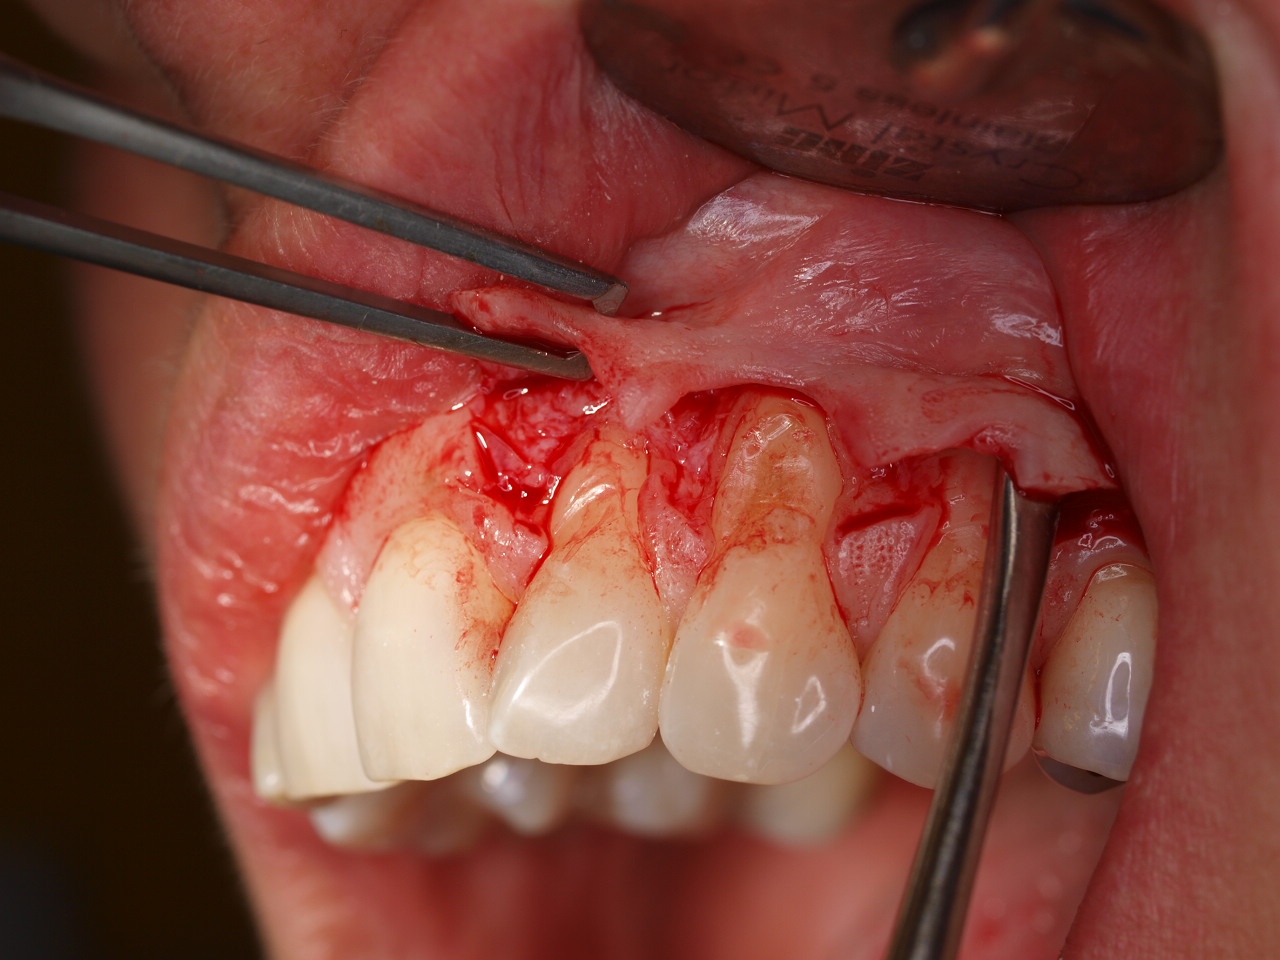

Multiple gingival recessions treated by MCAT with mucoderm® and Straumann® Emdogain® (2) - Rathe

Pre-operative clinical situation. Shallow multiple adjacent gingival recessions in the first quadrant.